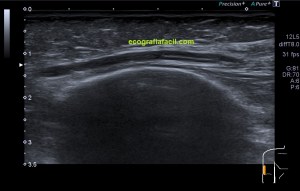

Estudiamos la región palmar del dedo en modo 2D, con una sonda de alta frecuencia, usando la máxima frecuencia de su rango dinámico, ajustando parámetros técnicos (pincha en los enlaces), como el foco, la frecuencia y la ganancia general, así como la profundidad y el rango dinámico para conseguir la mejor imagen posible, te lo muestro en la imagen 1.

En la imagen 1, tienes en un recuadro amarillo los datos de imagen que nos interesan y que te he contado en el párrafo superior y que te comento aquí:

Flecha azul: El Modo de trabajo de 2D, el más usado en ecografía clínica.

Flecha Blanca: Ganancia general, valor ajustable a cada paciente y que nos da el brillo de la imagen.

Flecha amarilla: Rango dinámico, valor que interviene en el contraste de la imagen.

Flecha rosa: Potencia de transmisión, la cantidad de energía a la que trabaja la sonda, es un porcentaje.

Recuadro rojo: Frecuencia usada, en este caso valor cualitativo, expresa frecuencia de resolución o máxima.

Recuadro azul: Profundidad utilizada, 2 centímetros, adecuada para una parte tan superficial.

Una vez revisadas las características técnicas de la imagen, pasamos a estudiar la ecoarquitectura. Mira:

Usamos gran cantidad de gel para no comprimir el pulpejo y poder estudiar las partes blandas de esta localización, obteniendo como resultado, esta imagen, número 2:

2

En esta imagen 2 observas el corte longitudinal de la región distal y flexora o palmar del tercer dedo, afectado por el traumatismo. Es una ecoanatomía normal. El hueso se observa hiperecogénico y liso, sin alteraciones en su ecoarquitectura, no hay soluciones de discontinuidad, a excepción de la articular correspondiente a la interfalángica distal, pero al desplazarme hasta la región más distal y estudiar el pulpejo del dedo, encuentro esta imagen: